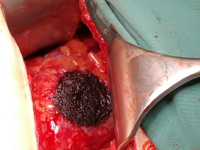

Przykład postępowania w przypadku guza II kości śródstopia pierwotnie podejrzewanego jako przerzut raka pęcherzykowatego tarczycy 40 i 20 lat po całkowitej tyroidektomii

Example of management of metatarsal bone II tumor originally suspected of having metastatic thyroid follicular cancer 40 and 20 years after total thyroidectomy